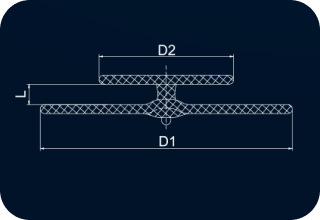

| Code | [D1]Right Disc Diameter(mm) |

[D2]Left Disc Diameter(mm) |

[L]Waist Length (mm) |

Minimum Recommended Sheath SizeSteerEase™(Fr.) |